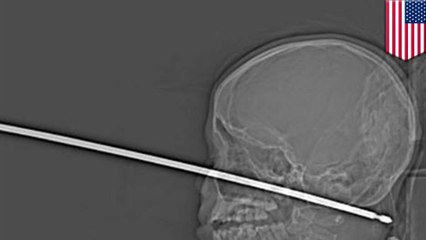

US boy survives after a meat skewer penetrates his skull

10-year-old Xavier Cunningham is recovering in hospital after falling from a tree and landing on a meat skewer which penetrated his skull. Report by Blairm.